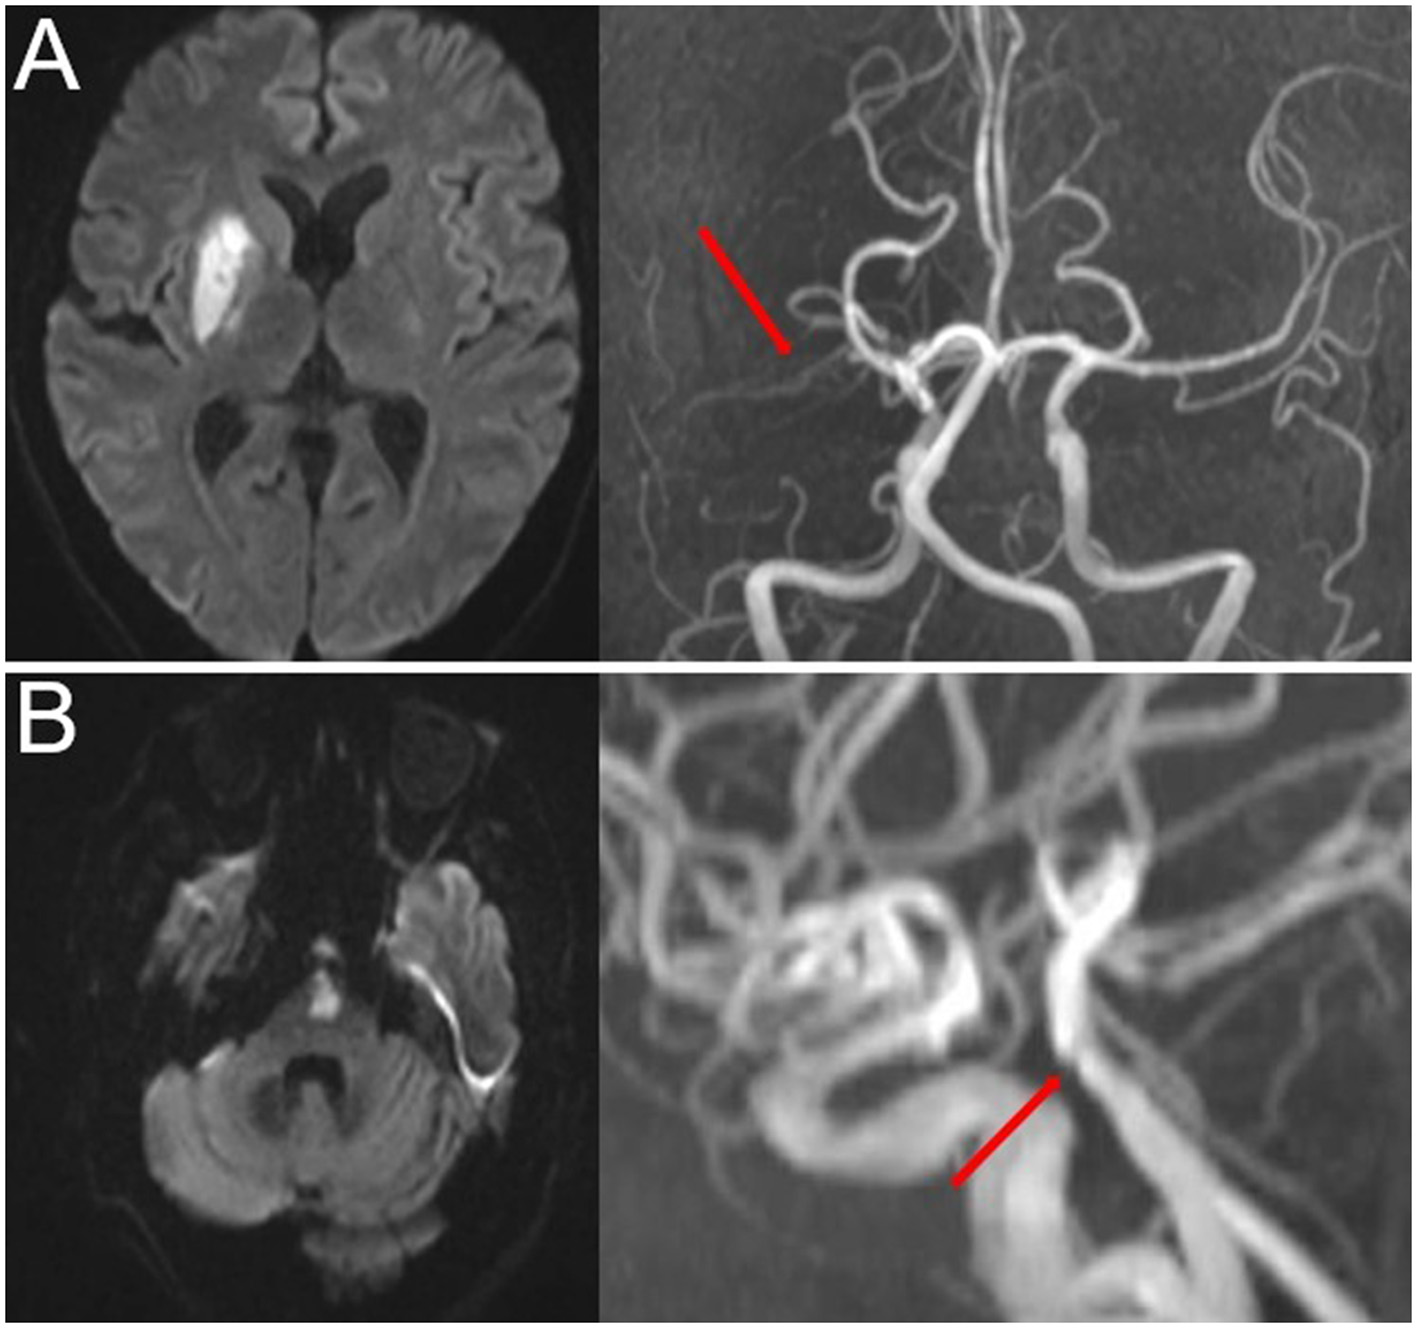

Time-of-flight magnetic resonance angiography (TOF-MRA) was used to detect intracranial atherosclerotic stenosis. The most commonly used parameters in TOF-MRA were as follows: flip angle = 20; TR = 30 ms; TE = 10 ms; slice thickness = 1.2 mm; and field of view = 230 mm. The degree of stenosis was evaluated using the Warfarin-Aspirin Symptomatic Intracranial Disease Study Trial method (24). PAD was defined as any degree of stenosis detected in the parent artery corresponding to SSI (15, 21) (Figure 2).

Figure 2

Representative cases of PAD. (A) Anterior SSI with PAD (red arrow) and (B) posterior SSI with PAD (red arrow). SSI, single subcortical infarction; PAD, parental arterial disease.